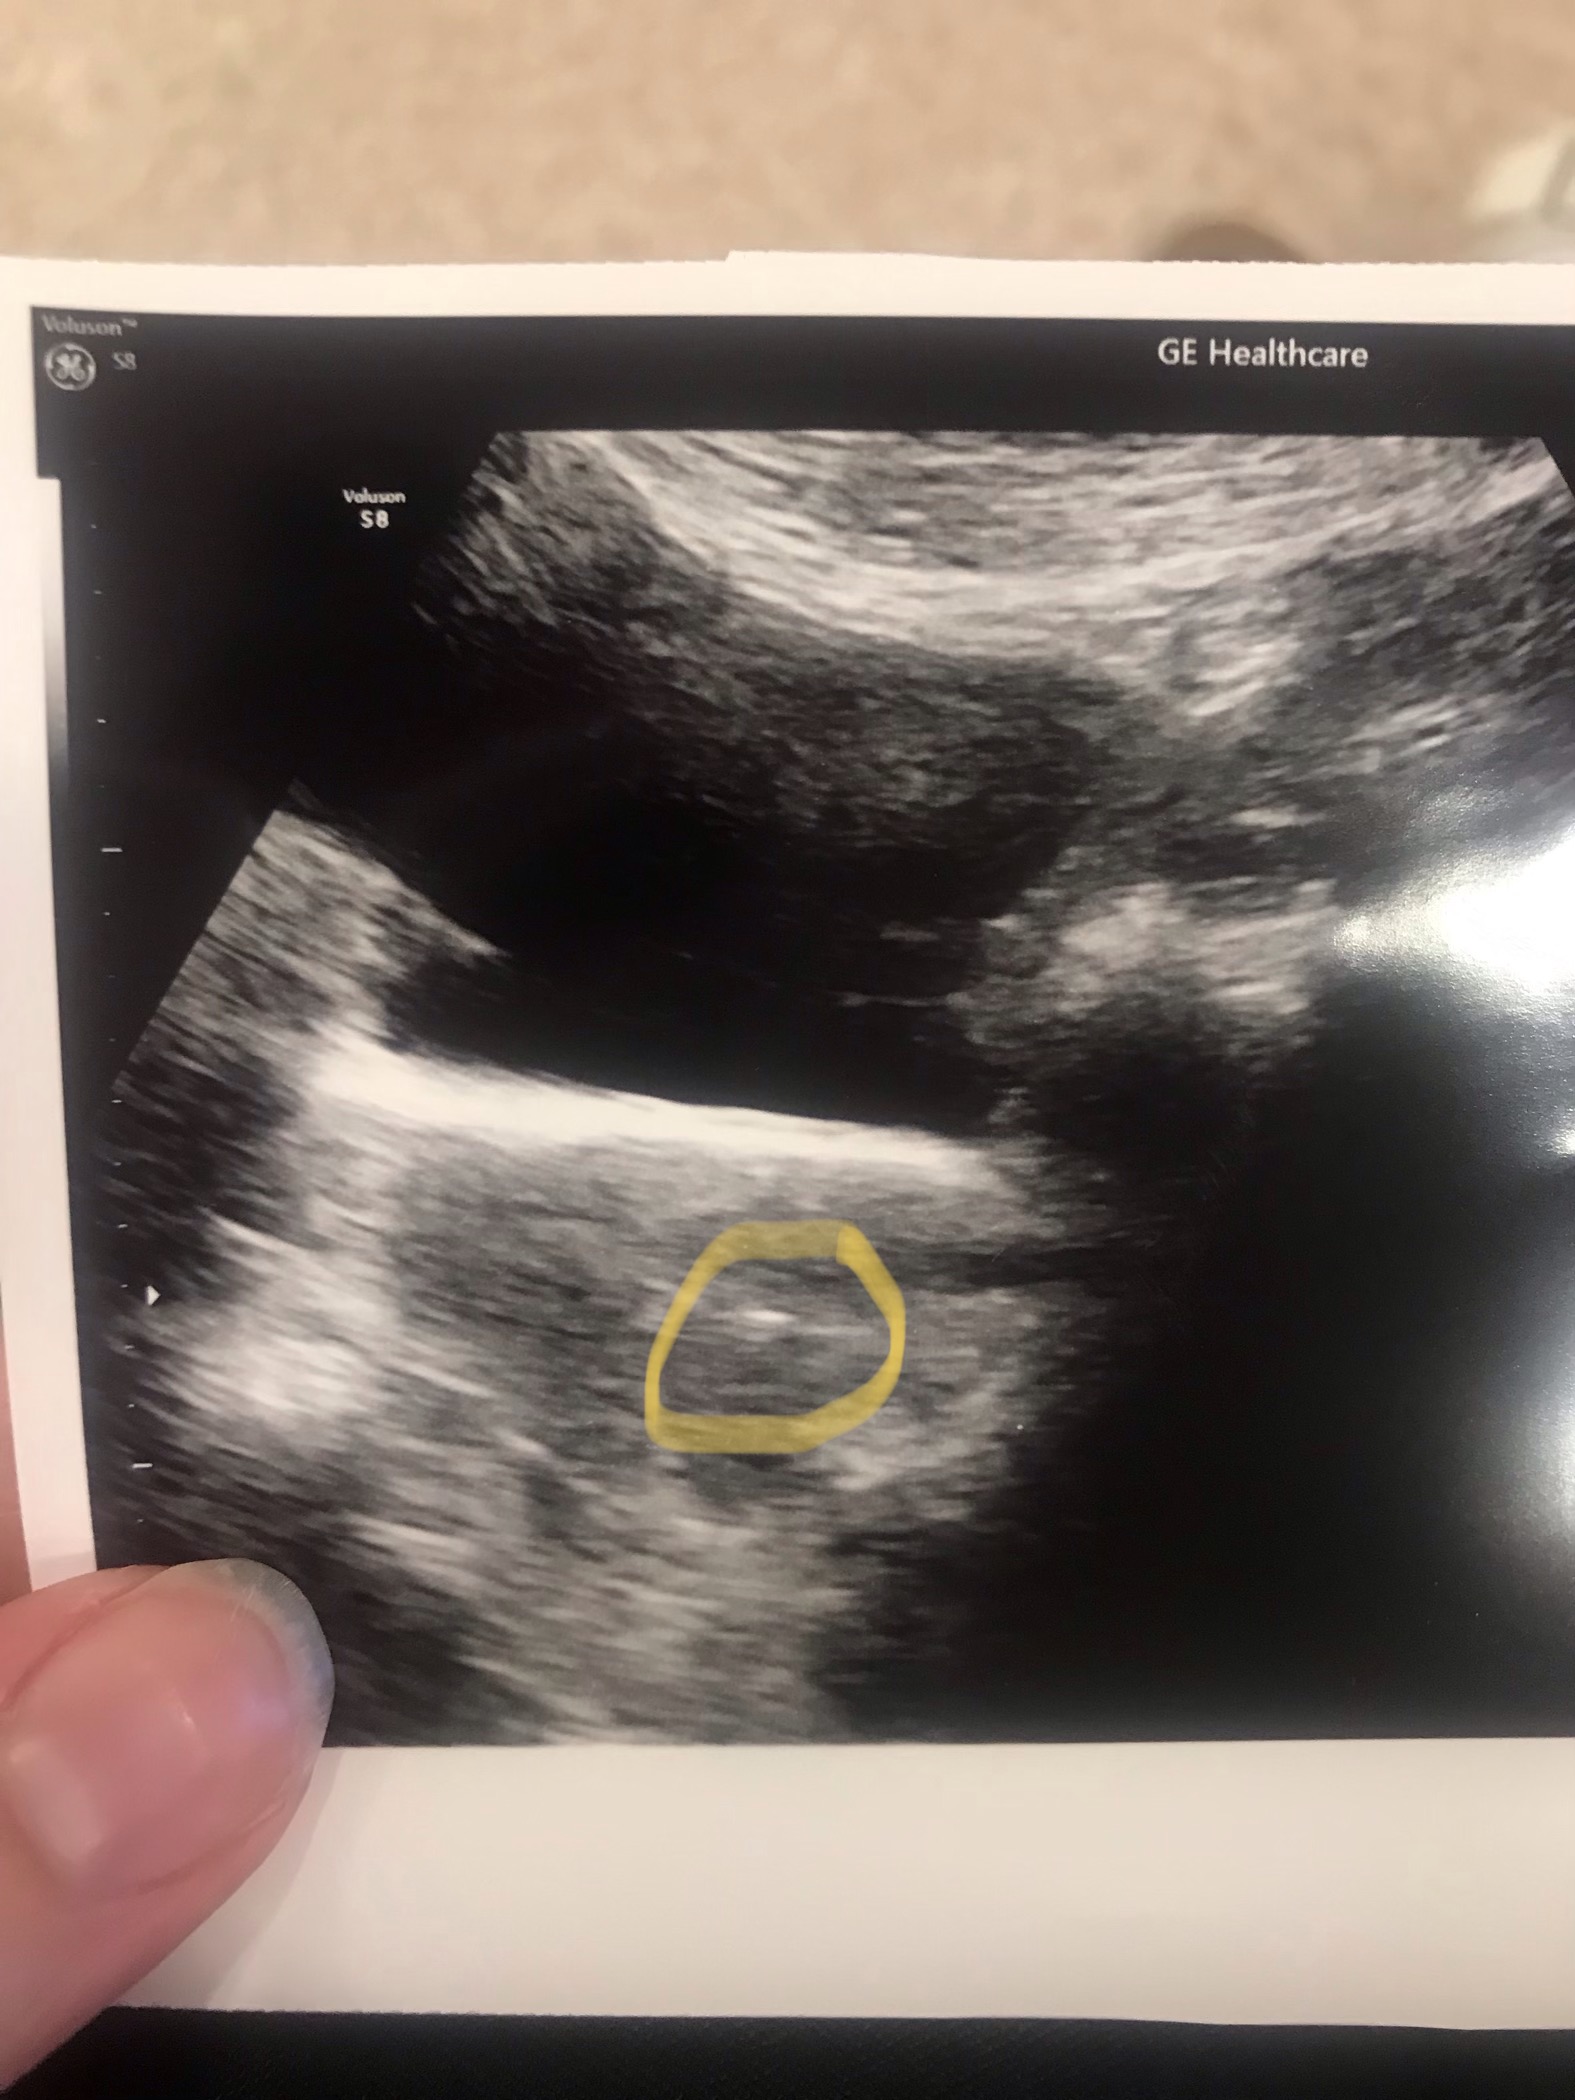

Fantastisk bilde!